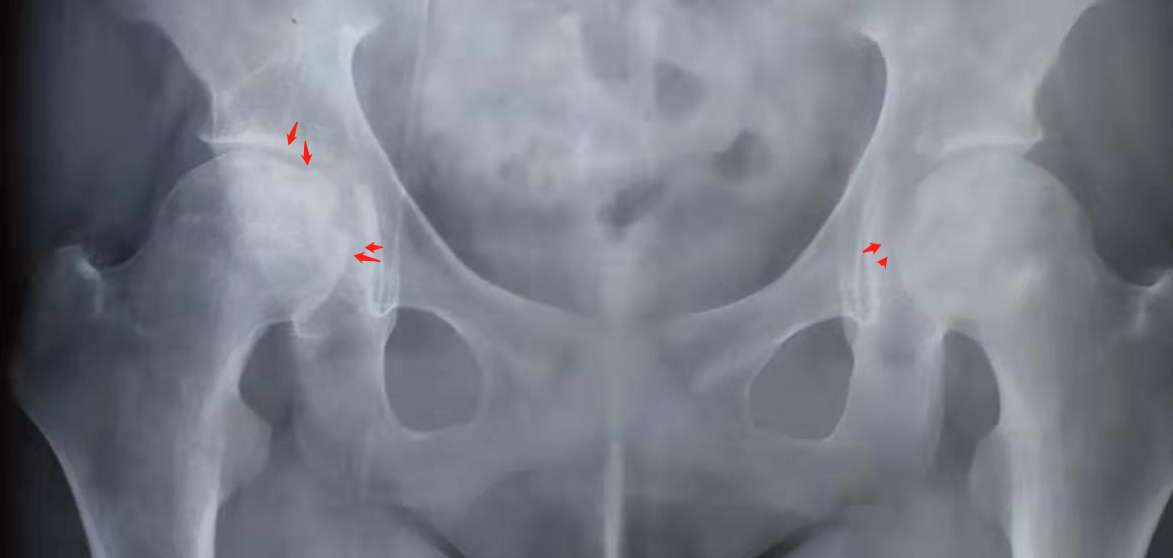

我感觉很多人,骨坏死了

我才吃一年半激素,也双侧骨坏了。拍DR看不出来,复查再拍磁共振才看到。